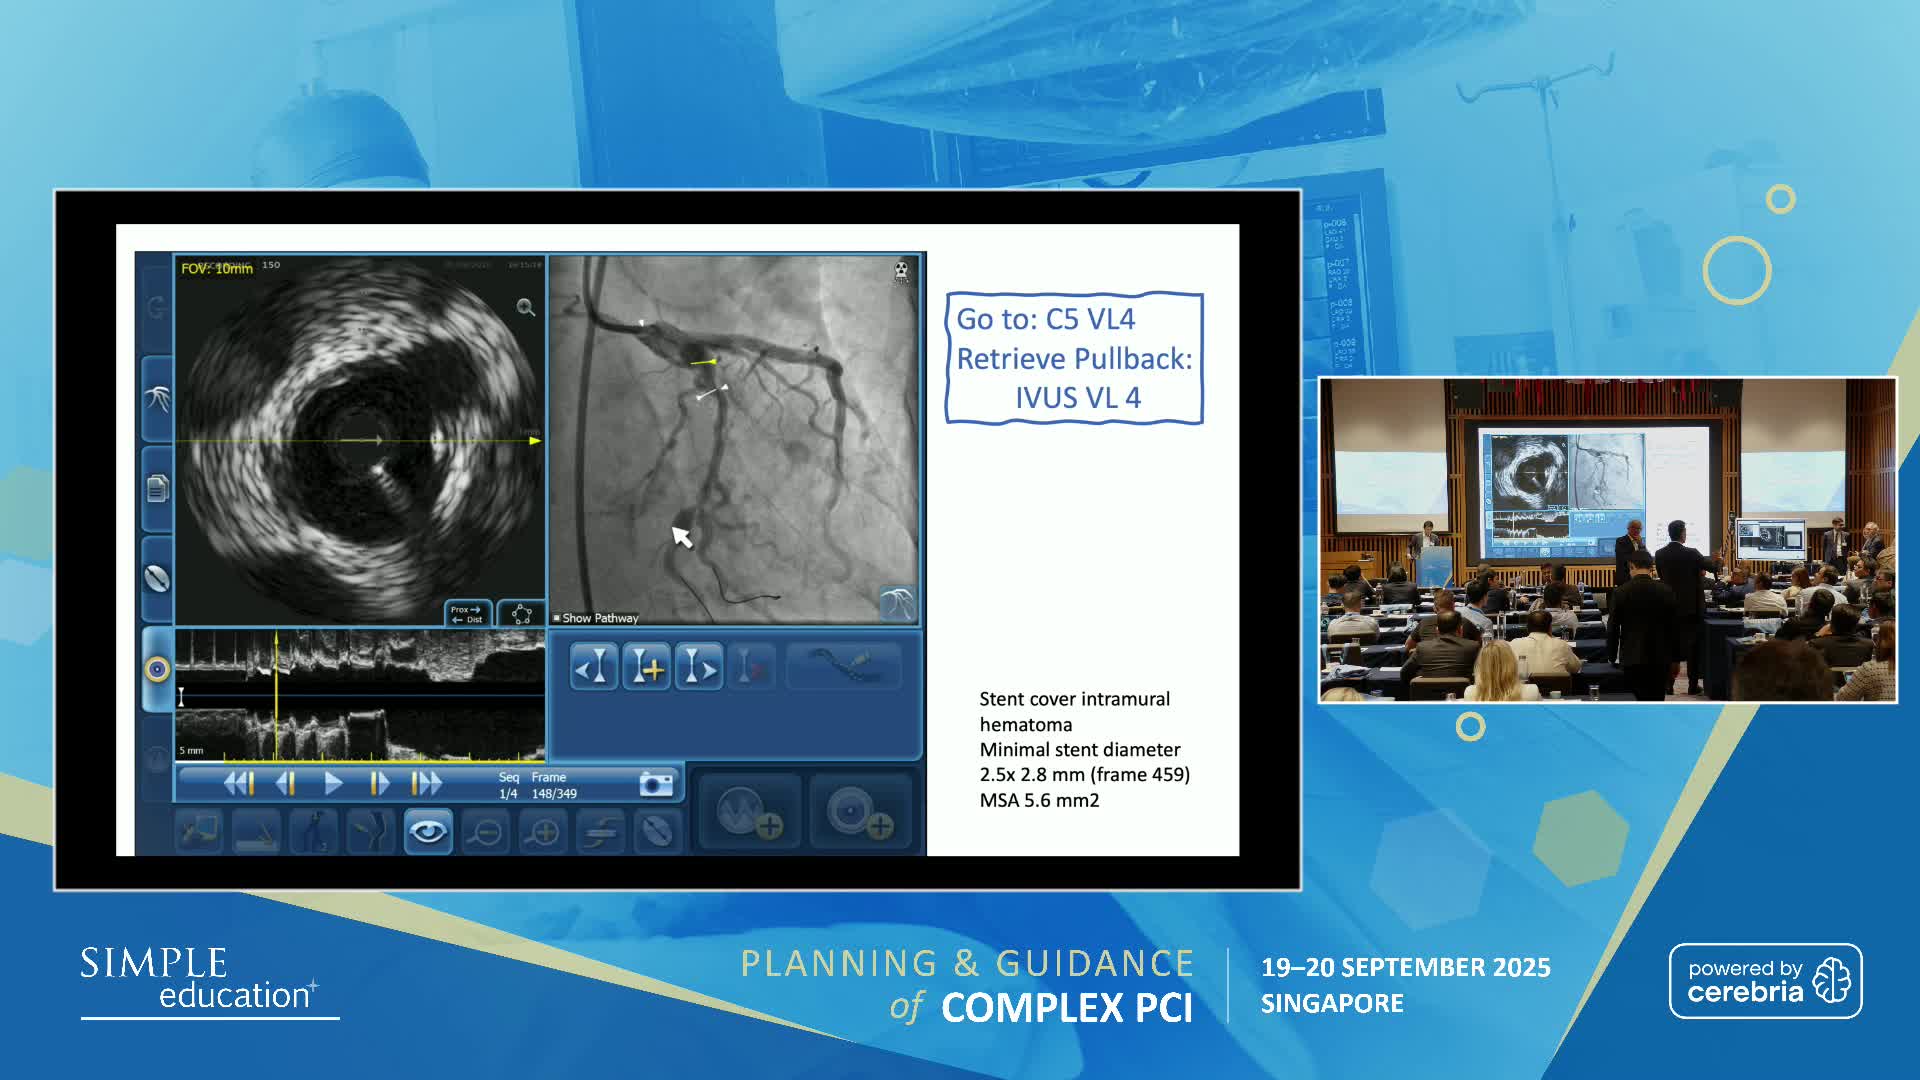

Planning and guidance of complex percutaneous coronary interventions - June 2023 Day One

Planning and guidance of complex percutaneous coronary interventions - June 2023 Day Two